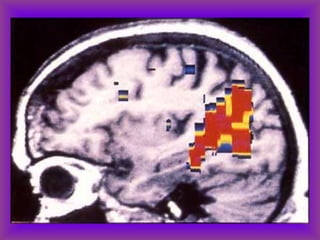

Types of fMRI

• BOLD-fMRI which measures regional differences in

oxygenated blood

• Diffusion-weighted fMRI which measures random

movement of water molecules. Diffusion tensor

imaging (DTI) measures diffusion of water in different

directions and is a good test for studying white

matter tracts.

• MRI spectroscopy which can measure certain

cerebral metabolites non-invasively

fMRI:Visual